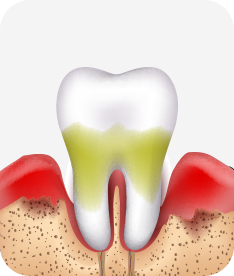

치은염 (초기~중기)

치아 주위의 잇몸이 붉게 부어 있으며, 칫솔질 등을 할 때 피가 남.

스케일링 주기의 조절이 필요할 수 있으며, 올바른 칫솔질을 시행하여야 함.

치주염 (중기~말기)

주기적으로 잇몸이 붓고 피가 나며, 욱씬하거나 우리한 통증이 나타남.

치주치료 및 정도에 따라 치주수술(잇몸수술)이 필요함. 향후 관리 정도에 따라 3~6개월 간격으로 내원하여 유지치료를 시행하여야 함.